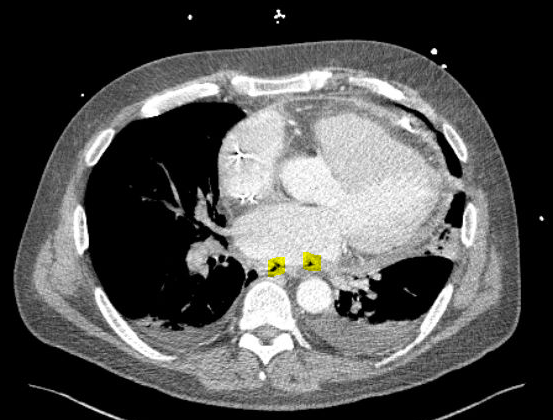

Case Presentation: A 62-year-old male with a history of paroxysmal atrial fibrillation presented with hypotension and 2 week history of chest pain after an ablation with pulmonary vein isolation. Transthoracic echocardiography demonstrated a pericardial effusion. Pericardial fluid sampling revealed an elevated leukocyte count of 130,000 cells per cubic millimeter and culture grew rare strep mitis/oralis and beta strep constellatus. While in the intensive care unit for vasopressor support, he developed left facial droop and hemiparesis, which spontaneously resolved within 1-2 hours. Initial non-contrast computed tomography (CT) of his head was unremarkable. He later became acutely altered with anisocoria and decerebrate posturing and repeat CT head was notable for pneumatosis cerebrii, consistent with air embolism. Computed tomography angiography (CTA) of the chest showed foci of gas within the posterior pericardial space adjacent to the left atrium (Figure 1A) concerning for atrio-esophageal fistula (AEF). No frank blood was found in his pericardial drain or oro-gastric tube and his hemoglobin remained stable. Cardiothoracic surgery performed an exploratory thoracotomy and repaired a left AEF.